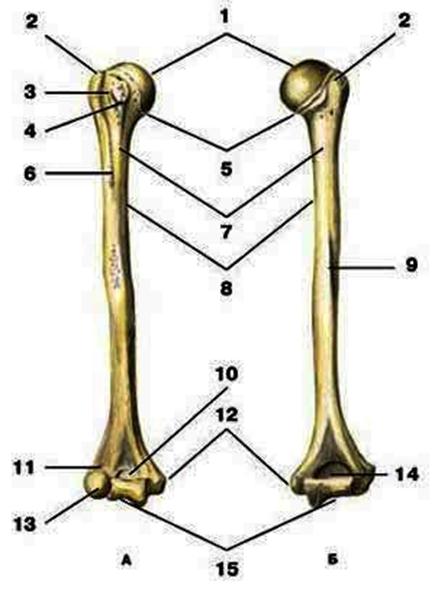

V2:Тема 1.3 Кости верхней конечности и их соединения

S: Цифра 1 обозначает … плечевой кости.

+:сaput

-:t uberculum majus

-:troсhlea

-:capitulum

-:epicondylus lateralis

S: Число 15 обозначает... плечевой кости.

+:trochlea

S: Цифра 5 указывает на...плечевой кости.

+:collum anatomicum

-:collum chirurgicum

S: Число 10 обозначает... плечевой кости.

+:fossa coronoidea

S: Число 14 указывает на... плечевой кости.

+:fossa olecrani

S: Цифра 9 указывает на... плечевой кости.

+:sulcus nervi radialis

S: Число 12 обозначает... плечевой кости.

+:epicondylus medialis